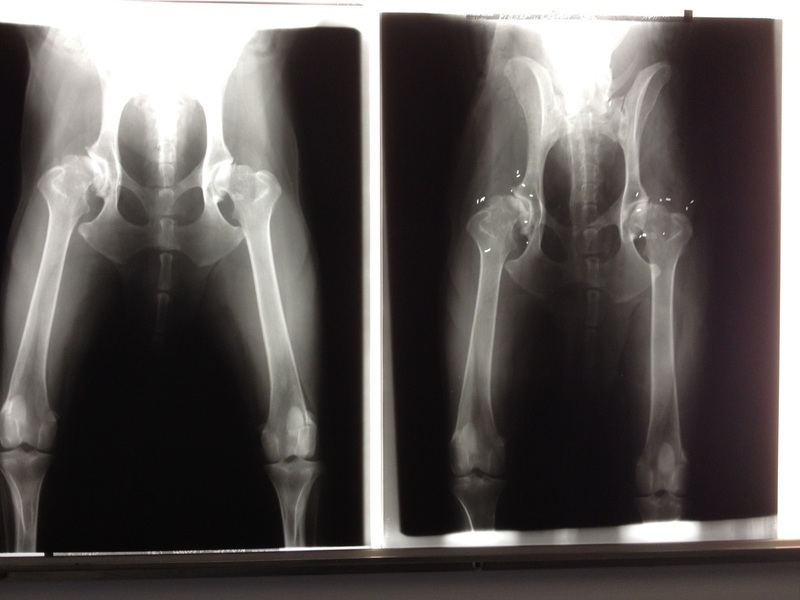

Die Goldimplantation / -akupunktur ist eine Möglichkeit, chronisch degenerative Gelenkerkrankungen zu behandeln. Sie kommt bei schmerzhaften Gelenkproblemen (u.a. Arthrosen, Wirbelsäulenerkrankungen, Dysplasien) zum Einsatz und ist oft eine hervorragende Therapie-Alternative oder auch eine letzte Hoffnung, dem Tier Schmerz zu ersparen, ihm sogar wieder Lebensqualität und nicht selten sichtbare Lebensfreude zu schenken. Mit einem Goldimplantat wird keine Heilung erzielt, d.h. es handelt sich um eine nebenwirkungsfreie symptomatische Therapie.

In einem ersten Schritt wird das Tier untersucht; es erfolgen gezielte Röntgenaufnahmen der Schmerzregion(en). Dabei wird festgestellt, inwieweit es in der betroffenen Region bereits zu sichtbaren Veränderungen gekommen ist. Dies hat Auswirkungen auf das Implantationsausmass, das Bewegungstraining und die Prognose.

Der Eingriff selber wird unter Vollnarkose durchgeführt. Eine Hohlnadel wird an das Ziel herangebracht. Die Einstichstellen befinden sich möglichst in Akupunktur- oder Triggerpunktnähe. Nun werden in den Konus der Nadel ein bis drei, ca. 1 - 3 mm lange, sterile 995 Karat Reinstgoldstücke eingelegt und an den jeweils vorher ausgewählten Punkten, Arealen, bzw. Zonen implantiert. Die Goldimplantate werden vom Körper nicht als "fremder Eindringling" wahrgenommen. Daher wachsen die "Goldstücke" ohne Probleme im Gewebe ein und verbleiben dort, wo sie eingesetzt worden sind.